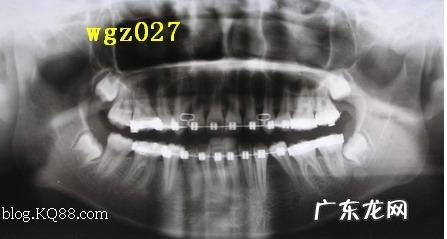

3、患牙列拥挤

口腔环境不合适是导致种植牙失败的重要原因 。一般来说 , 患者的牙列拥挤 , 是造成种植牙失败的重要原因之一 。因此 , 我们在进行种植牙之前需要检查自己所患牙是否存在拥挤 , 并进行矫正 。如果你感觉自己的牙齿比较拥挤 , 那么你必须得到更多的关注 。因为你的牙齿已经是拥挤得很严重了 。为了保证牙齿正常咀嚼功能 , 种植牙不应该暴露出来 。牙列拥挤是非常严重的身体疾病需要及时处理 。这就是为什么人们认为种植牙会导致严重拥挤的原因之一 。